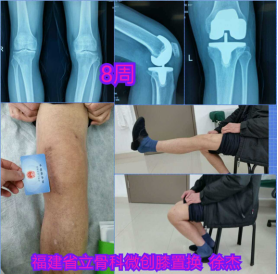

近日,我院对口帮扶的云霄县医院骨科孙伯辰主治医师,在国际知名杂志《Orthopaedic Surgery》(中科院二区)上,以第一作者身份成功发表文章,题为《股内侧肌下入路运动学对线与机械学对线全膝关节置换术后髌骨轨迹的比较》。该文通讯作者为我院副院长、骨科学科带头人徐杰教授。

自2015年起,徐杰教授团队采用创新的股内侧肌下全膝关节置换术治疗严重膝骨关节病,这种保留肌肉不切开的手术仅有一张社保卡长度的小切口,取得了当天下地、一天出院、三天上楼梯的快速康复显著成效。

2017年,团队在大陆最早开展运动学对线的膝置换,并将肌下微创手术与运动学表面置换结合起来成为新术式在国际上首先报道,吸引美国、东南亚等地华侨回国手术,积累了大量病例。几年来,全国各地许多医生来我院参访该创新手术。

✅ 临床-科研双赋能:孙伯辰医师在我院攻读硕士期间,依托省立病例库完成核心数据研究,新术式保留肌肉更彻底,术后髌骨轨迹更优;